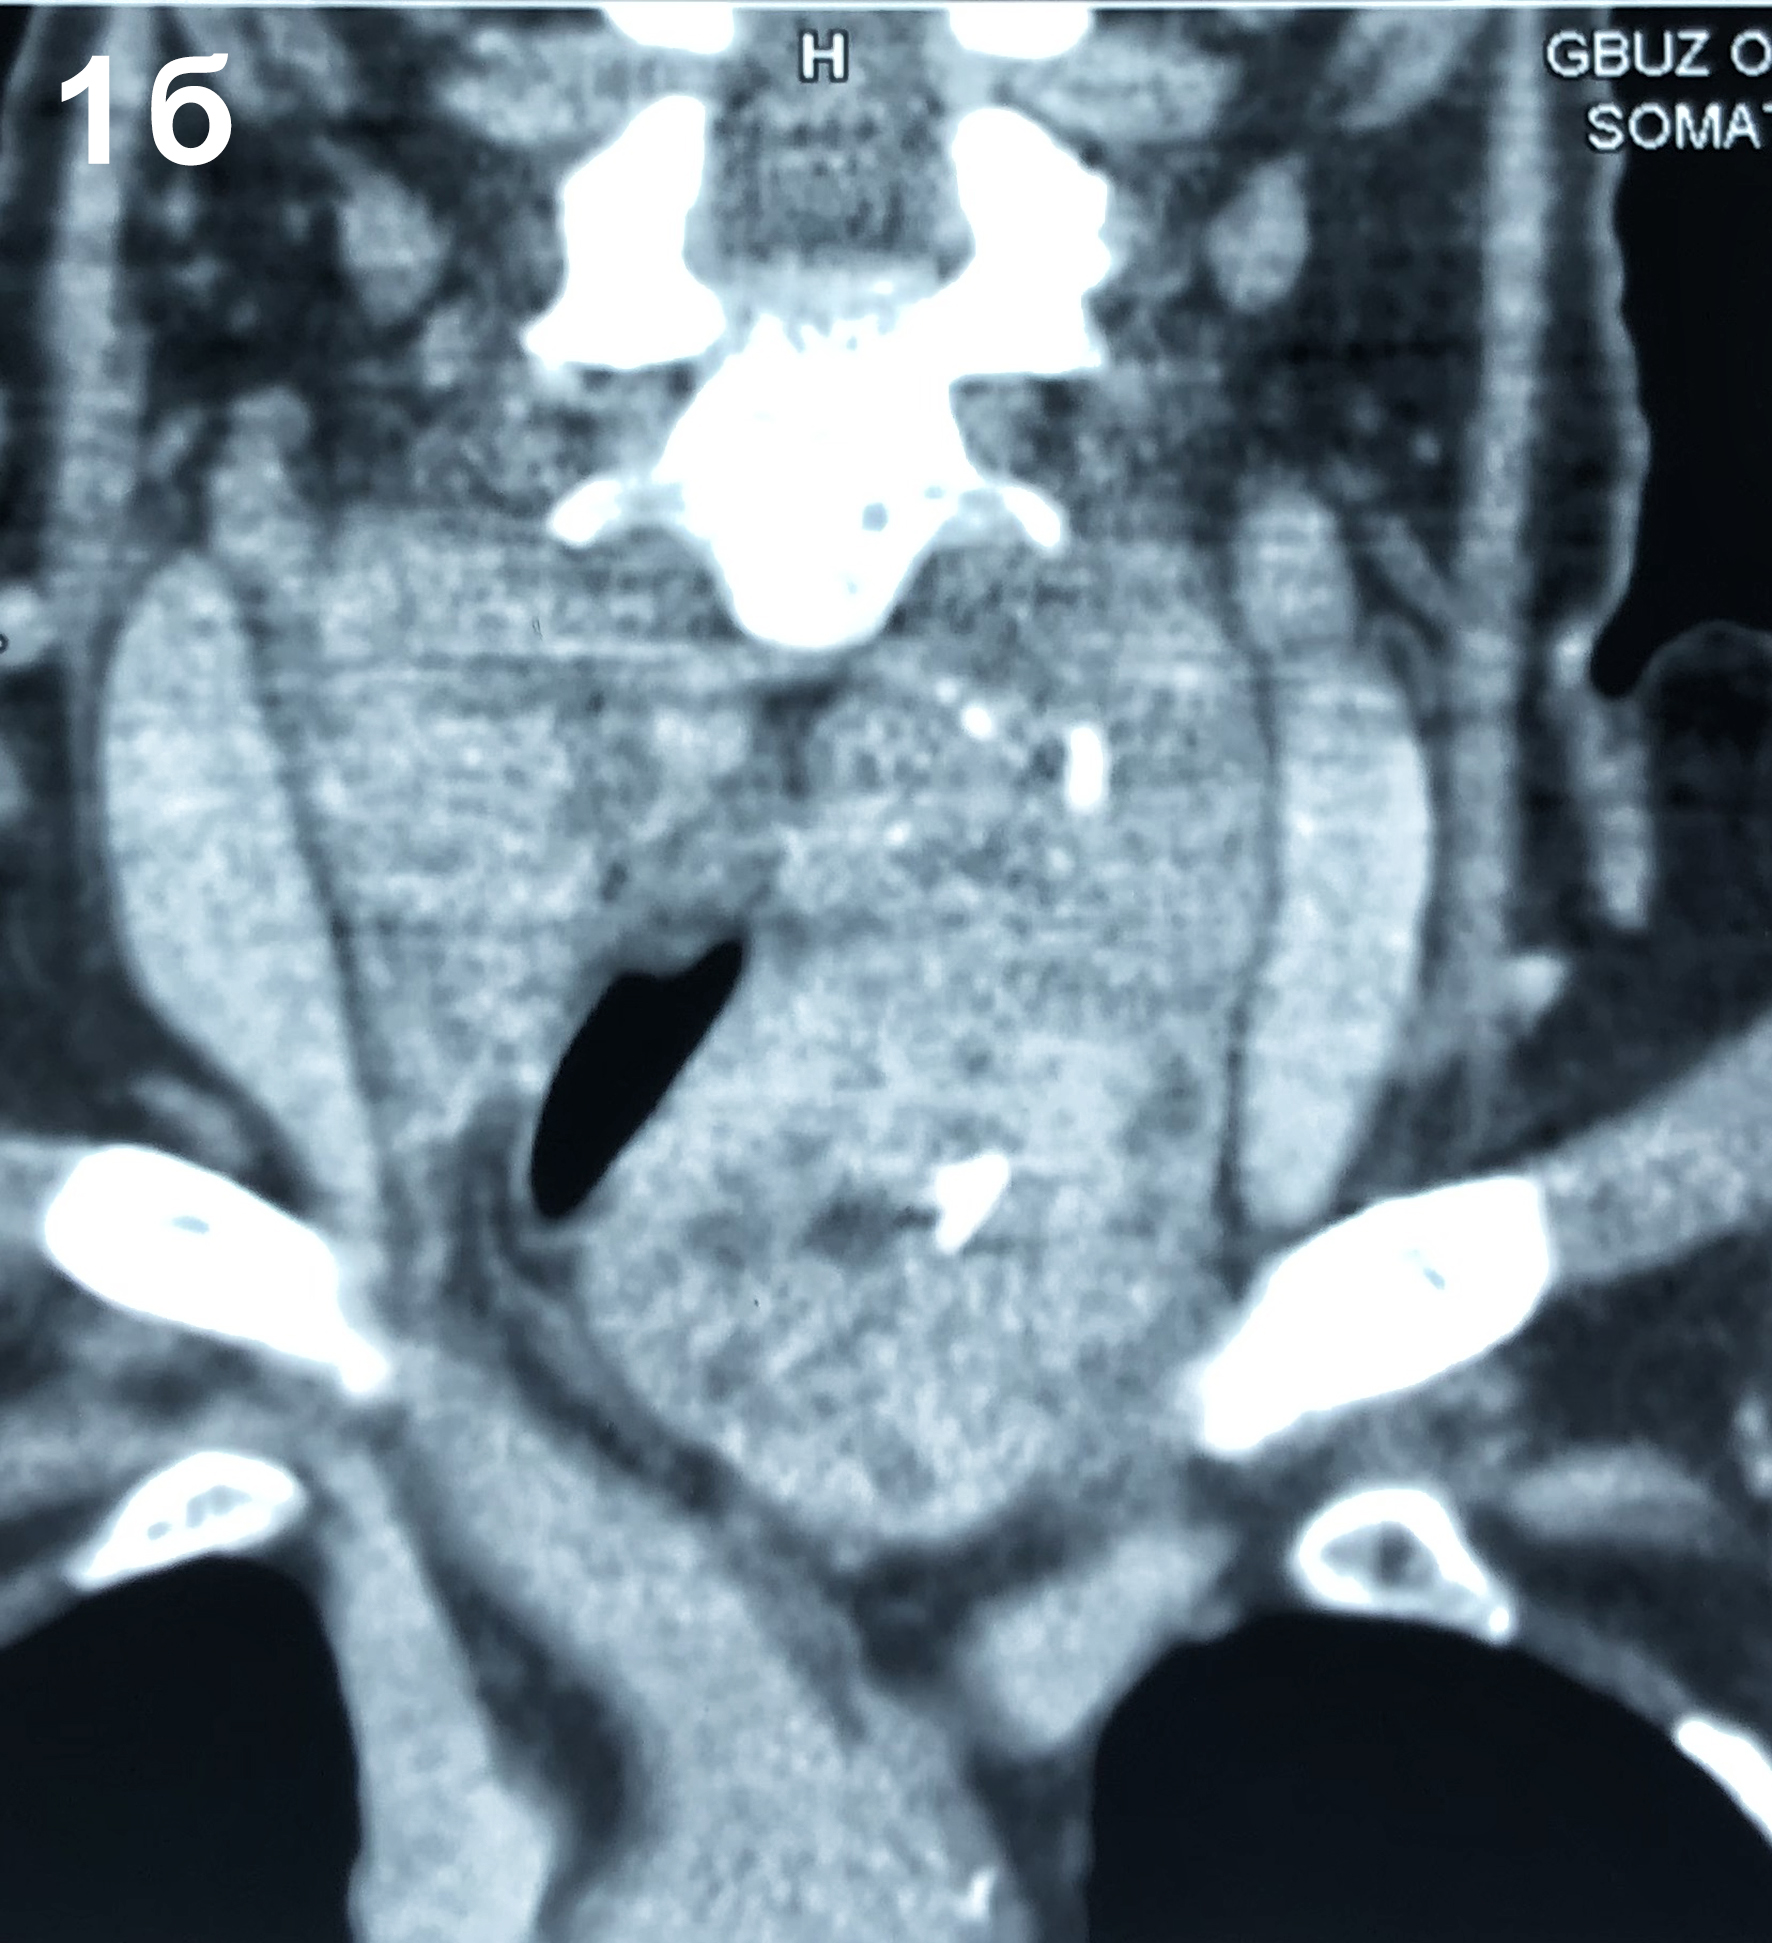

1. Рисунок 1a, b. Компьютерная томография шеи: диффузное увеличение щитовидной железы за счёт обеих долей с распространением загрудинно. Верхние полюса достигают сосцевидных отростков. Сужение просвета трахеи до 5 мм. | |

2. Рисунок 1a, b. Компьютерная томография шеи: диффузное увеличение щитовидной железы за счёт обеих долей с распространением загрудинно. Верхние полюса достигают сосцевидных отростков. Сужение просвета трахеи до 5 мм. | |